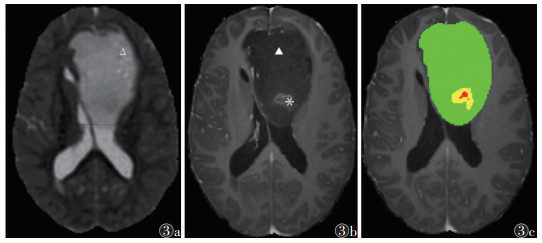

| 注:患者,男,43岁;图3a为RD图,可见瘤周水肿远侧区域呈高信号(Δ);图3b,3c分别为T1WI增强扫描图像、分割图像,可见肿瘤强化范围较小(图3b*,图3c黄色区域),瘤周水肿范围大(图3b▲,图3c绿色区域),即体积比强化/水肿小 图 3 Ⅳ级星形细胞瘤异柠檬酸脱氢酶(IDH)突变型的体积比强化/水肿及径向扩散率(RD)图 |

![]() |

ROC曲线显示,AUC及约登指数最高的参数分别为FA水肿近侧、体积比强化/水肿、RD水肿近侧、RD水肿远侧、MD水肿远侧,其敏感度分别为0.750、0.909、0.800、0.900、0.850,特异度分别为0.779、0.571、0.634、0.572、0.579(表 2)。对上述参数进行联合诊断,联合诊断预测因子=exp(-2.398×体积比强化/水肿-14.017×FA水肿近侧-4.648×MD水肿远侧+1.890×RD水肿近侧+7.482×RD水肿远侧-3.770),当截断值为0.162时,敏感度为0.800,特异度为0.826,约登指数为0.626,AUC为0.866,诊断效能优于各参数单独诊断(图 2)。对上述参数进行串联及并联试验,结果表明,各参数串联试验诊断效能均有提升,RD水肿远侧与体积比强化/水肿这一组合的约登指数最高,其次分别是MD水肿远侧与体积比强化/水肿、FA水肿近侧与体积比强化/水肿、MD水肿远侧与RD水肿远侧、RD水肿远侧与FA水肿近侧(表 3)。体积比强化/水肿小而RD水肿远侧高为IDH突变的可能更高(图 3,4)。